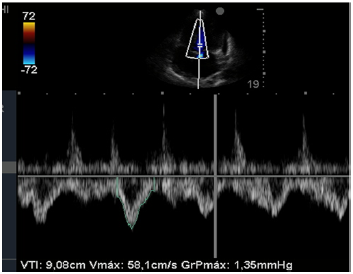

Insonação cardíaca Janela apical 5 câmaras com VTI de 9,08 cm

Enunciado 4334998-4

O nefrologista foi chamado a opinar na melhor conduta para o paciente. Para tanto, realizou uma ultrassonografia beira leito pulmonar e mensurou a velocidade integral tempo (VTI) do trato de saída do ventrículo esquerdo. Chegou, assim, à conclusão que poderia ser feita uma expansão no paciente. Com base nas imagens apresentadas, é correto afirmar que conduta recomendada pelo nefrologista está